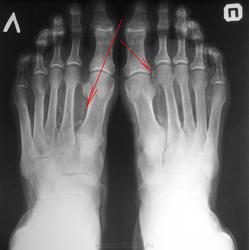

Что за тени указанные стрелками?

Пожилой мужчина пришёл на исследование кистей и стоп. Меня заинтересовали продольные нитевидные тени, указанные красными стрелками. Моё мнение что это склеротические изменения артерий.

Обызвествления стенок сосудов. Сахарным диабетом пациент не болеет?

Значит болеет. Картина характерна для артериосклероза Менкеберга. Хотя (если не подтвердится) артериосклероз может быть и другой этиологии

Артериосклероз Менкеберга (кальцифицирующий склероз средней сосудистой оболочки) развивается у пациентов старше 50 лет. Возрастная дегенерация средней сосудистой оболочки происходит с фокусами кальцификации и даже формированием костной ткани в пределах артериальной стенки. Участки артерии могут стать твердой кальцифицированной трубкой без сужения просвета.

Диагноз обычно становится очевидным при простом рентгенологическом исследовании. Клиническое значение этого заболевания заключается только в том, что артерия не способна реагировать изменением просвета, что приводит к выраженному, но ложному повышению цифр АД при его изменении.

Рис. б). Рентгенограмма стоп больного со склерозом Менкеберга на фоне сахарного диабета: стрелками указаны кальцифицированные артерии тыла стопы.